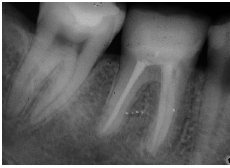

Preparación dentaria en #26 para EC. Obsérvese el chamfer en. vestibular, distal y palatino

Control radiográfico a los 10 años..